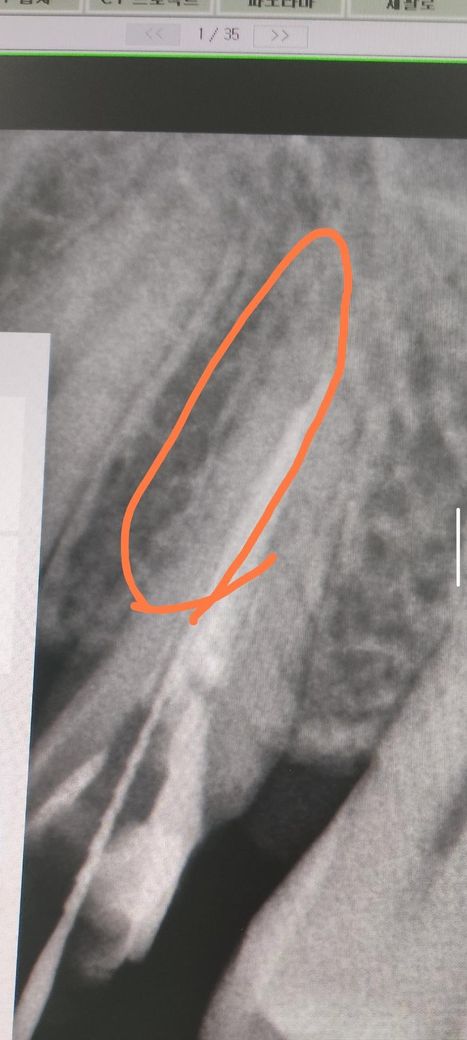

치아 뿌리 수직파절인지 사진 한번만 봐주세요

치아뿌리 파절의심이 들어 발치할려고 하는데

치아뿌리 파절이 맞을까요 사진상으로 동그라미친 부위

치아뿌리 수직 파절양상이 보이거나 맞는지 한번만 봐주시면

참고로 두사진 같은 치아입니다

지금 사진만으로는 흐릿해서 정확히 알 수 없습니다. 수직치근 파절이라면 여러 각도에서 찍어야 crack이 보일 수 있고, crack 자체의 선이 희미하다면 x-ray나 ct 상에서 보이지 않을 수 있습니다. 즉 지금 자료로는 금이 갔다 가지 않았다 판단하기에 애매한 부분이 있습니다.